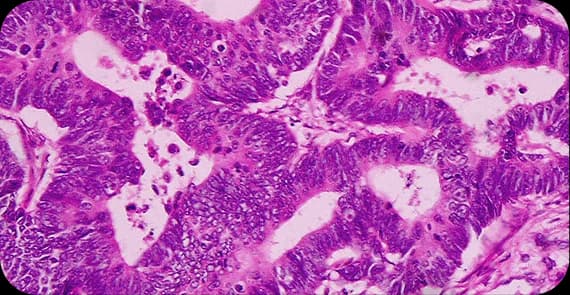

When patients ask what gallbladder cancer is, the explanation begins at the cellular level. Gallbladder cancer occurs when cells in the inner lining of the gallbladder develop genetic mutations that cause uncontrolled growth.

In many cases, chronic inflammation of the gallbladder may contribute to these cellular changes. What happens in gallbladder cancer is a gradual transformation of normal cells into malignant cells that may invade the liver or nearby structures if left untreated.

There are different types of gallbladder cancer depending on the cell origin.

The most common type, arising from glandular cells lining the gallbladder.

A subtype that may grow more slowly compared to other forms.

A rare form arising from squamous cells in the gallbladder.

These may include neuroendocrine tumours or sarcomas.